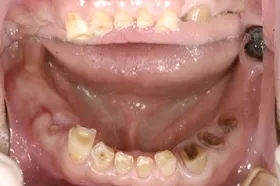

■治療前

■治療後

| 主訴 | しっかりかみたい(咬合障害) |

| 治療方法 | 費用を抑える為、全てインプラントではなく、インプラントを土台とした入れ歯の治療 |

| 治療期間 | 約6か月 |

| 通院回数等 | 約20回 |

| 費用 | 約150万円 |

| リスク・副作用 | 術後の腫れ・痛み |